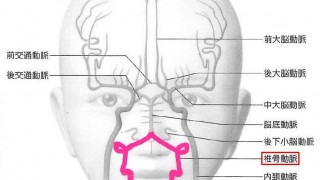

未破裂脳動脈瘤の破裂リスク(UCAS Japan,PHASEスコア)

UCAS Japanの示した未破裂脳動脈瘤の破裂危険度2001年1月〜2004年4月まで新患登録最長2009年まで経過観察前向き大規模コホー...